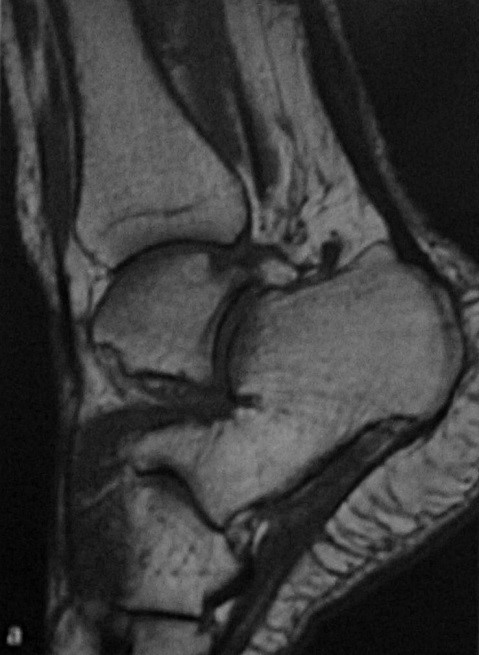

a,b Частичный разрыв ахиллова сухожилия: (a) Т1-взвешенная МРТ. Гиперинтенсивная веретиновидная припухлость в средней трети ахиллова сухожилия;

(b) МРТ после введения контрастного вещества. Частичный разрыв четко ограничен продольными и вертикальными участками накопления контрастного вещества

a,b МРТ при разрыве ахиллова сухожилия: (a) Полный разрыв проксимального конца ахиллова сухожилия после мышечно-сухожильного соединения

(b) Отрыв дистального конца в проекции прикрепления сухожилия к пяточной кости

Благодаря магнитно-резонансной томографии даже самые мелкие дефекты сухожилия могут быть обнаружены. Это идеальное исследование, оно дает высококачественные изображения, поэтому оно может быть особенно полезно в неясных случаях или для запланированной операции. С помощью магнитно-резонансной томографии (МРТ) можно точно увидеть все связочные структуры и сопутствующие травмы, пяточную шпору ; признаки деформации Хаглунда и бурсита . Тем не менее, МРТ назначается только в том случае, если выздоровление идет медленными темпами или если подозревается более серьезная травма из-за механизма несчастного случая. Для стандартной диагностики не используется.

- Визуализация всего ахиллова сухожилия, особенно при подозрении на неполный разрыв

- Утолщение сухожилия

- Полный разрыв

- В поздней стадии - участки дегенерации (тендинит) и истончения сухожилия

- При неполном разрыве (редко) может наблюдаться изолированный, внутрисухожильный

- частичный разрыв волокон

- Сопутствующие нарушения: бурсит, тендинит.